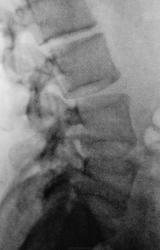

И вот, с обоснованием в истории болезни, пациентку на "носилках" доставили в рентгеновский кабинет для рентгенографии поясничного отдела позвоночника. Исследование было проведено в положении лёжа.

Боли в пояснице весьма объяснимы ступенчатой комбинацией ретролистезов поясничных позвонков.

Пусть назначат антибиотики. Ранние признаки спондилодисцита невозможно разглядеть доже на таких приличных спондилограммах. Смущают диски Д11-Д12 и Л5-S1. Нужно уточнить локализацию болей в пояснице. Так как МРТ и КТ недоступны, можно попробовать линейные томограммы, но лучше недели через 2-3, тогда станет виднее. А пока назначить антибиотики.

Рентгенограмма и томограммы произведены были в положении лежа, и поза у пациентки вынужденная, она действительно не может лежать на спине, болевой синдром, лежа на спине действительно очень сильный. По всей видимости, "прогрессирование сколиоза", больше вызвано анталгической позой.

Точно. Не понятно: почему спина болит, что с дужкой L3, почему раздутый кишечник весь в малом тазу...